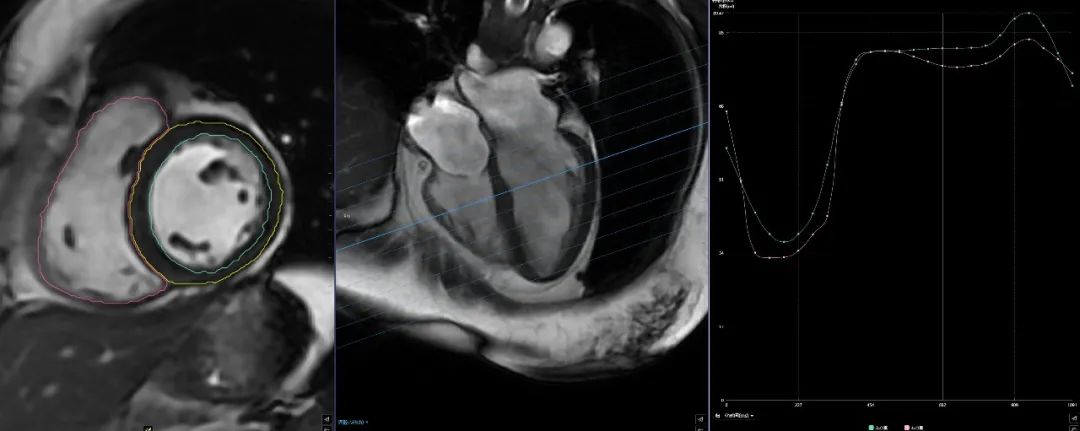

(二)心臟磁共振“一站式”檢查,通過多種掃描序列對心臟進(jìn)行綜合成像,具有無電離輻射、大視野、任意平面成像等優(yōu)點,可重復(fù)性強(qiáng),空間、時間和軟組織分辨力良好,還可以實現(xiàn)在體組織“病理影像化”。

圖片

心臟磁共振“一站式”檢查